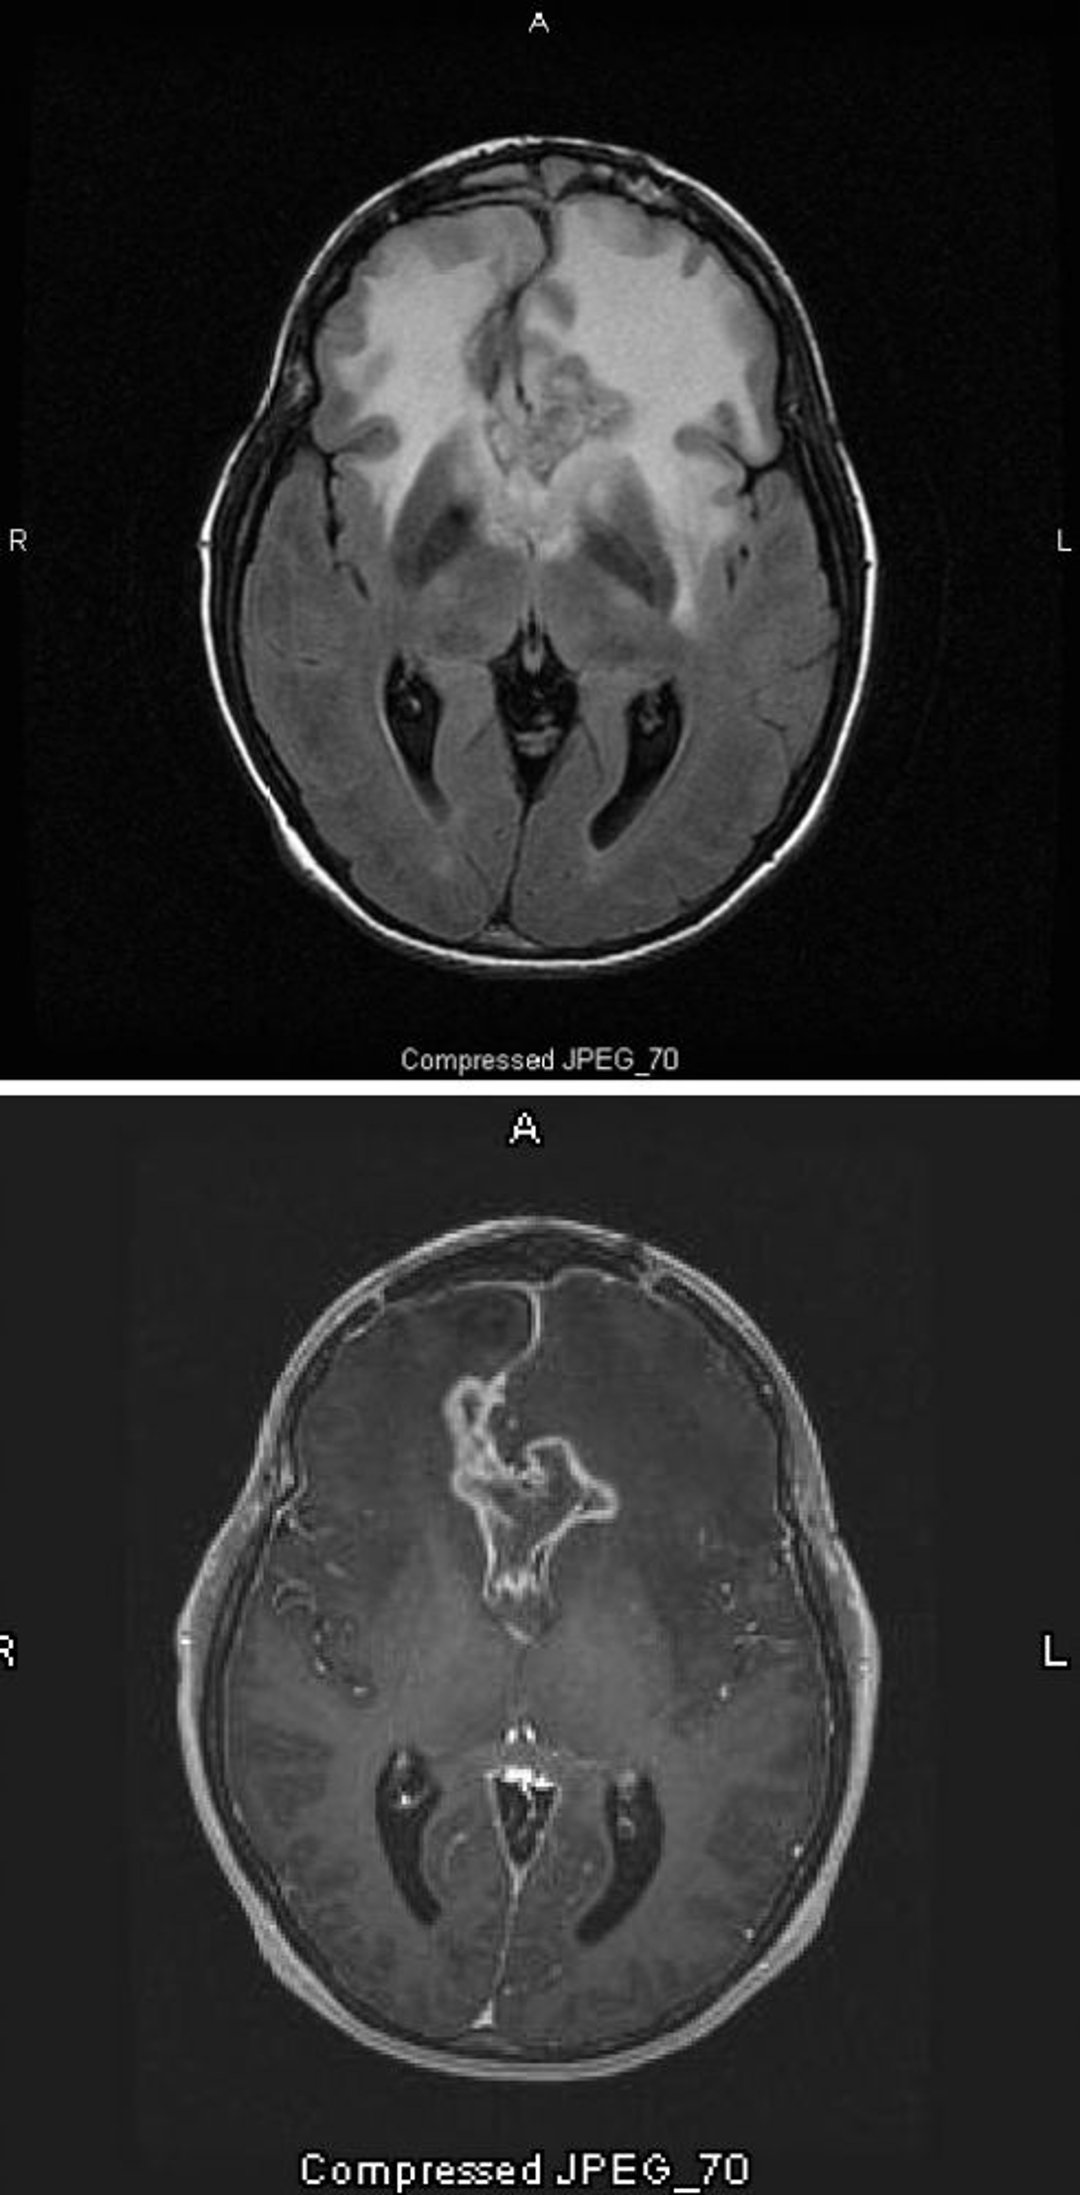

Glioblastoma

La scansione RM T2-FLAIR (fluid-attenuating inversion recovery) (in alto) mostra un grande segnale bianco bilaterale (iperdensità) attorno al glioblastoma, che è l’astrocitoma con il più alto grado di malignità. Questo particolare glioblastoma è chiamato glioma a farfalla perché il segnale bianco attorno al tumore forma le ali della farfalla; è causato da edema cerebrale. Nella scansione pesata in T1 (in basso), il contrasto delinea il bordo del tumore (enhancement dell'anello). L'edema appare come un'area scura (ipointensità) al T1.

Images courtesy of William R. Shapiro, MD.